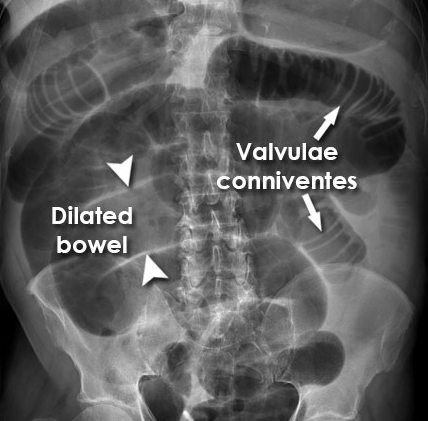

Describe what is seen in this AXR [3]

A

Small bowel obstruction - features

Centrally located multiple dilated loops of gas filled bowel (arrowheads)

Valvulae conniventes (arrow) are visible - confirming this is small bowel